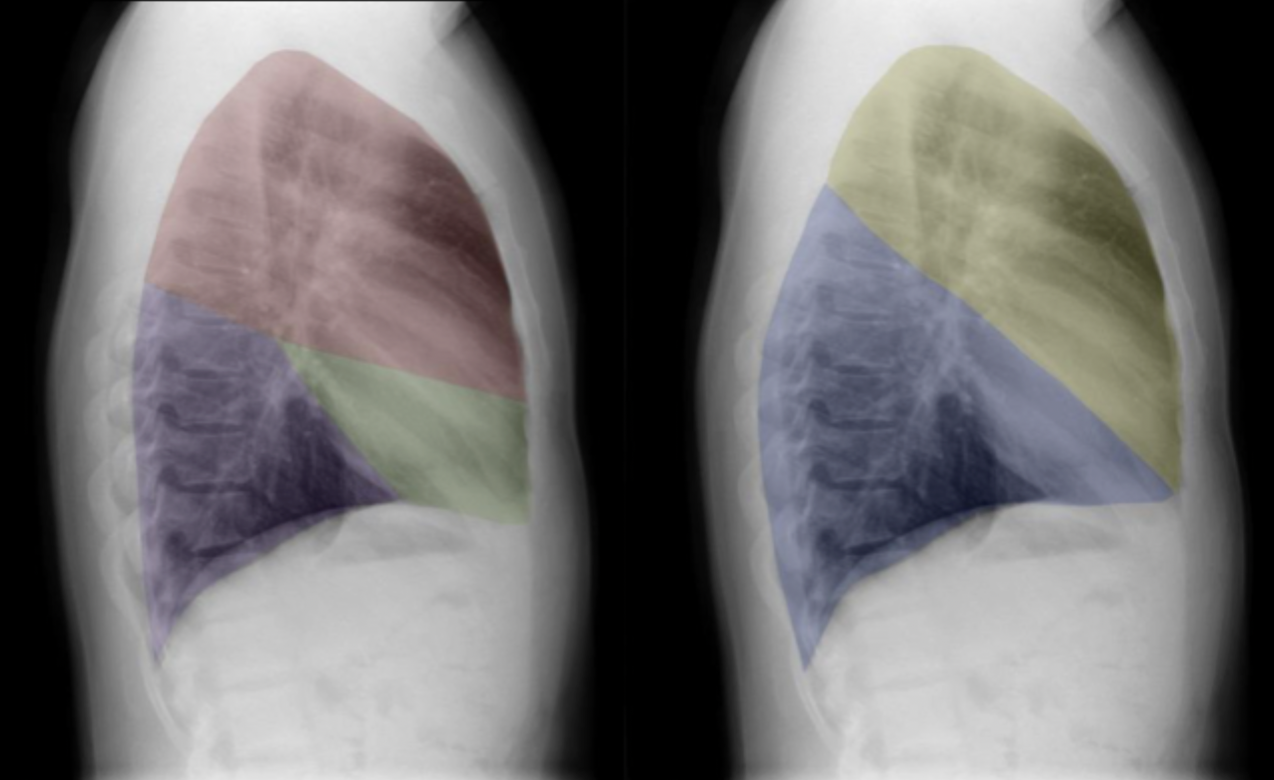

6

Q

Which lobe is which ?

A

Red: right upper lobe (RUL)

Green: right middle lobe (RML)

Purple: right lower lobe (RLL)

Yellow: left upper lobe (LUL)

Blue: left lower lobe (LLL)

How well did you know this?

7

8

9

The lingular segments of the left upper lobe abut the left heart border, so can be thought of as anatomically equivalent to the middle lobe in the right lung.

“Abut” means: to lie next to or to directly touch.